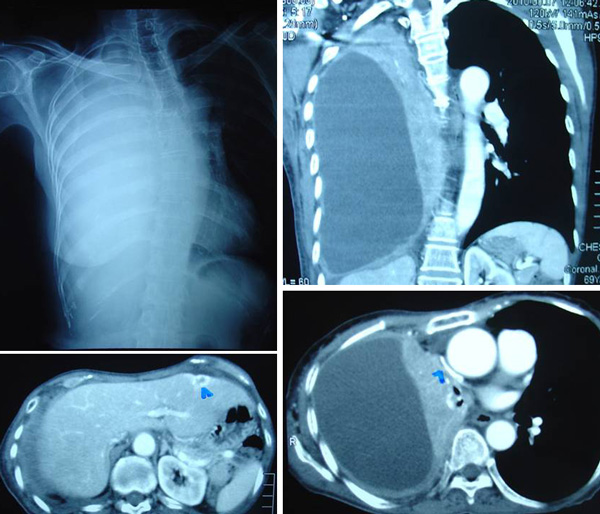

Henry, a 54-year old male, came to see us on 24 April 2009. He told us that he had spent about RM 300,000 to cure his lung cancer but failed. He could not see how medical science could help him any more. Also, he had spent enough money and probably is not able to spend anymore chasing after his cancer. Below is a brief outline of what had happened.

1. Henry was then 50 years old. Sometime in September 2003, he started to have persistent coughs. Antibiotics did not help him. An X-ray, done in November 2003, showed presence of a 1.5 cm lump in his left lung.

2. Henry went to Singapore and did a PET scan on 23 December 2003. The findings wereconsistent with a primary tumour of the left lower lobe without evidence of hilar or mediastinal nodal spread or distant metastatic spread. PET staging is T1NoMo.

3. The next day, a FNAC biopsy was done and indicated Non-small cell carcinoma.

4. Henry returned to Penang and underwent a surgery – a left upper lobectomy on 7 January 2004.  Pathologic diagnosis confirmed a moderately differentiated adenocarcinoma of the bronchus with foci of squamoid differentiation. There was no evidence of nodal involvement, i.e. Stage 1 disease.

5. No additional therapy was advised and Henry remained well until late September 2004, i.e. barely nine months after the operation.

6. His blood test on 27 September 2004 showed elevated CEA, at  21.1.

7. A PET scan done on 29 September 2004, showed evidence of recurrent disease. Moderately FDG avid small soft tissue density adjacent to surgical bed, with one FDG avid precarinal node. This was suspicious of local recurrence. There were 2 nodules measuring 1.1 x 1.9 x 1.7 cm and 1.1 x 1.5 x 1.7 cm. There was no evidence of distant involvement.

15. On 25 August 2007, a CT scan showed a new 1 cm nodule in the anterior segment of the right upper lobe, highly suspicious for metastatic recurrence. The means that the cancer had spread to Henry’s right lung.

16. PET scan done on the same day, 25 August 2007, confirmed the development of a new nodule.

17. A CT scan done on 11 October 2008 showed the nodule had grown to 1.9 x 1.4 cm. In view of the recurrence, the consumption of Tarceva was increased from 100 mg to 150 mg.

18. Another repeat PET scan was done three months later, on 1 December 2008. The nodule in the right upper lobe showed marked increase in FGD activity and is in keeping with active metastatic disease. The nodule increased in size to 2.0 x 1.7 cm.

20. A CT scan done on 23 January 2009, showed the right upper lobe nodule remained unchanged.

21. On 8 April 2009, Henry underwent a radiofrequency ablation (RFA) – a   procedure that cost RM 7,000. The lung nodule at this stage had already grown to 3 x 2.4 x 2.5 cm. The medical report said: Successful percutaneuos CT guided RFA is performed. A good ablation zone is achieved. A repeat CT scan after 6 weeks is scheduled.